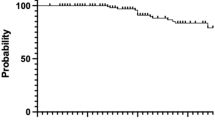

Median follow-up was 61.8 (range 0.5–147.3) months. The 5‑year biochemical relapse-free survival (bRFS) was 85.4% for all patients and 93.3, 87.4, and 79.4% for low-, intermediate-, and high-risk disease (Fig. 3). For high-risk patients 5‑year bRFS was 90.9% with androgen deprivation therapy and 55.4% without (p = 0.008, Fig. 4). For the cohort of intermediate-risk patients androgen deprivation therapy did not significantly influence bRFS.

The 5‑year prostate-specific survival (PSS) was 94.8% for all patients and 98.7, 98.9, and 89.3% for low-, intermediate-, and high-risk disease, respectively. 10-year prostate-specific survival was 92.4%. The 5‑ and 10-year overall survival rates were 83.8 and 66.3%, respectively.

During follow-up 27 patients developed distant metastasis, resulting in 5‑ and 10-year freedom from distant metastasis rates of 92.2 and 88%, respectively. 5‑year freedom from distant metastasis was 98.7, 95.5, and 87.0% for low-, intermediate-, and high-risk disease, respectively (Fig. 5). Androgen deprivation therapy did not significantly influence freedom from distant metastasis in any risk group.